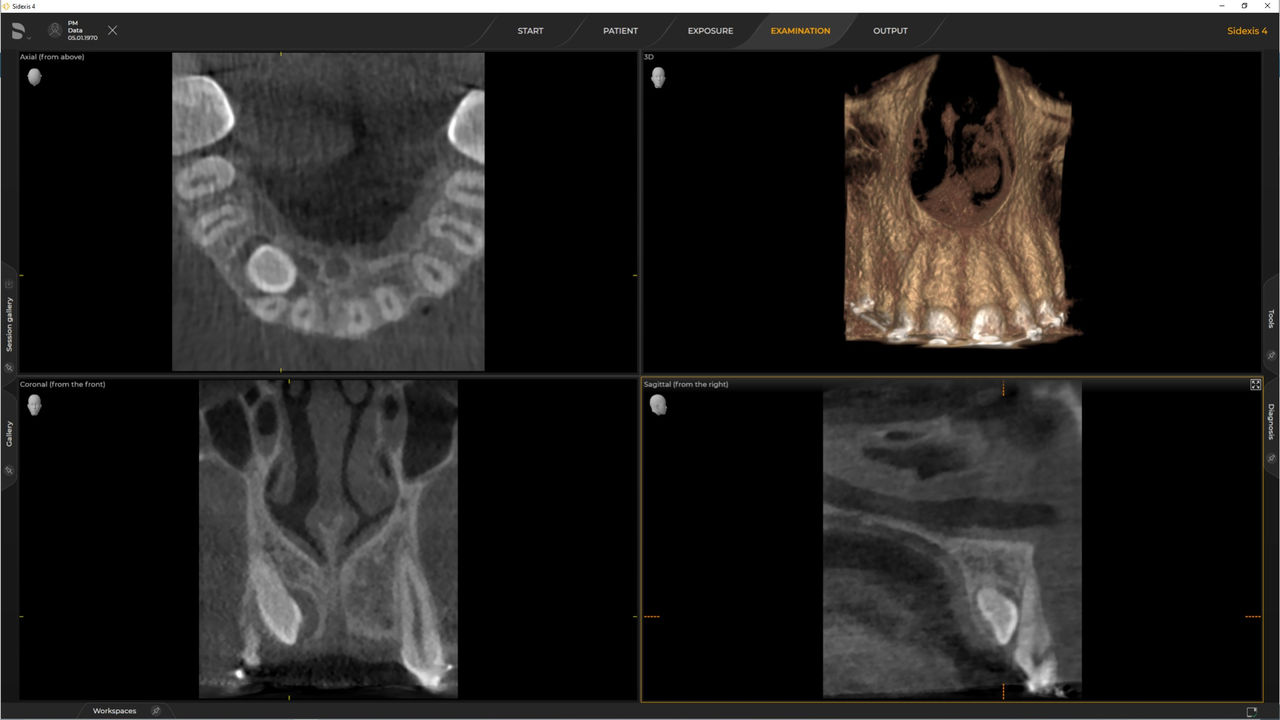

Con el modo de dosis baja inteligente 3D, obtiene imágenes 3D en el rango de dosis de una imagen radiológica 2D. En el modo HD (hasta 1400), las imágenes individuales se obtienen durante una única rotación y se convierten en un volumen 3D con hasta 80 μm para imágenes de bajo ruido en alta resolución.

Una amplia gama de tamaños de volumen para satisfacer sus diversas necesidades clínicas y de diagnóstico, desde Ø 5 x 5,5 cm hasta Ø 11 x 10 cm